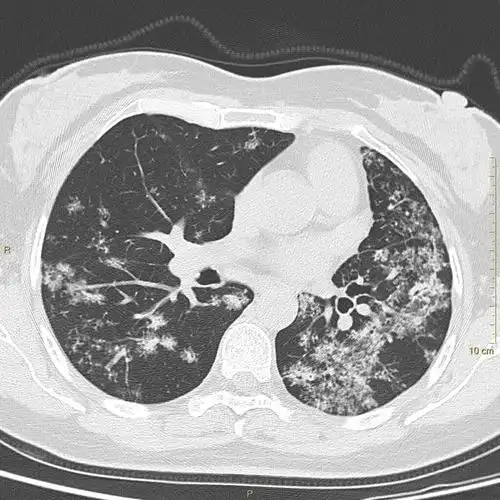

肺结核之烟花征——黄勇老师经典病例分享